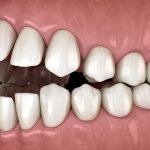

• отсутствие одного зуба;

• отсутствие 2-х и более зубных органов, при соседнем расположении;

• отсутствие последних зубов без возможности восстановления иными методами;